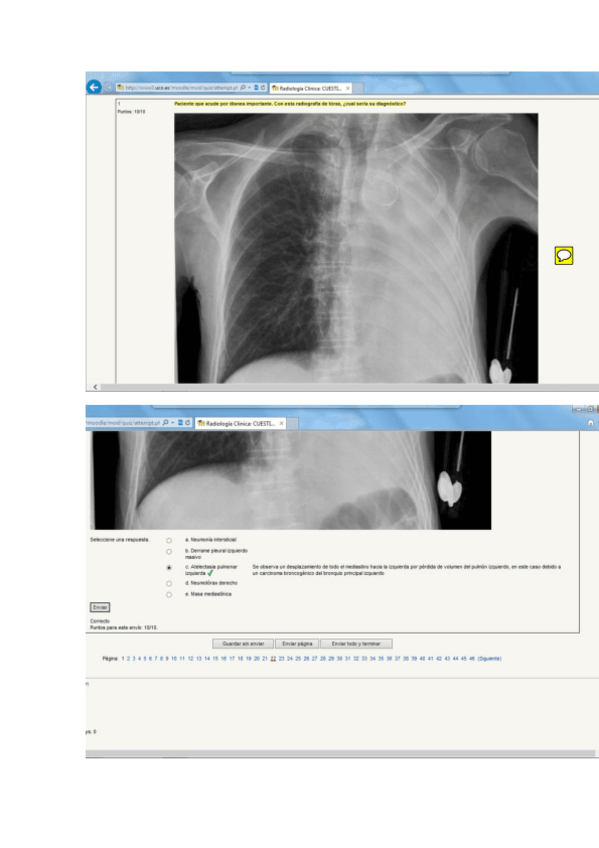

Radiología Clínica

Exámenes - EXAMEN RADIOLOGÍA CLÍNICA tipo B - PRIMERA CONVOCATORIA DICIEMBRE- CURSO 2018-2019.docx

Ejercicios - Autoevaluación 2017.docx

Exámenes - Test RadioDx.pdf

Exámenes - Examen 2018.pdf

Exámenes - Preguntas-Febrero-2019.pdf

Exámenes - EXAMEN-RADIO-DICIEMBRE-2020.pdf

Exámenes - Conjunto-Examenes-varios-anos.pdf

Exámenes - Examen-2015.pdf

Exámenes - Examen-2006.pdf